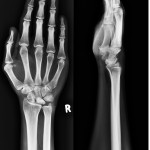

Image Quiz 10 #Wrist

What are your treatment options? Use the Poll and write your answers in the Comments section below. Popular Answer may not imply right answer. Follow our twitter handle for the right answer, https://twitter.com/drhiteshg/status/567308751305076736?s=01